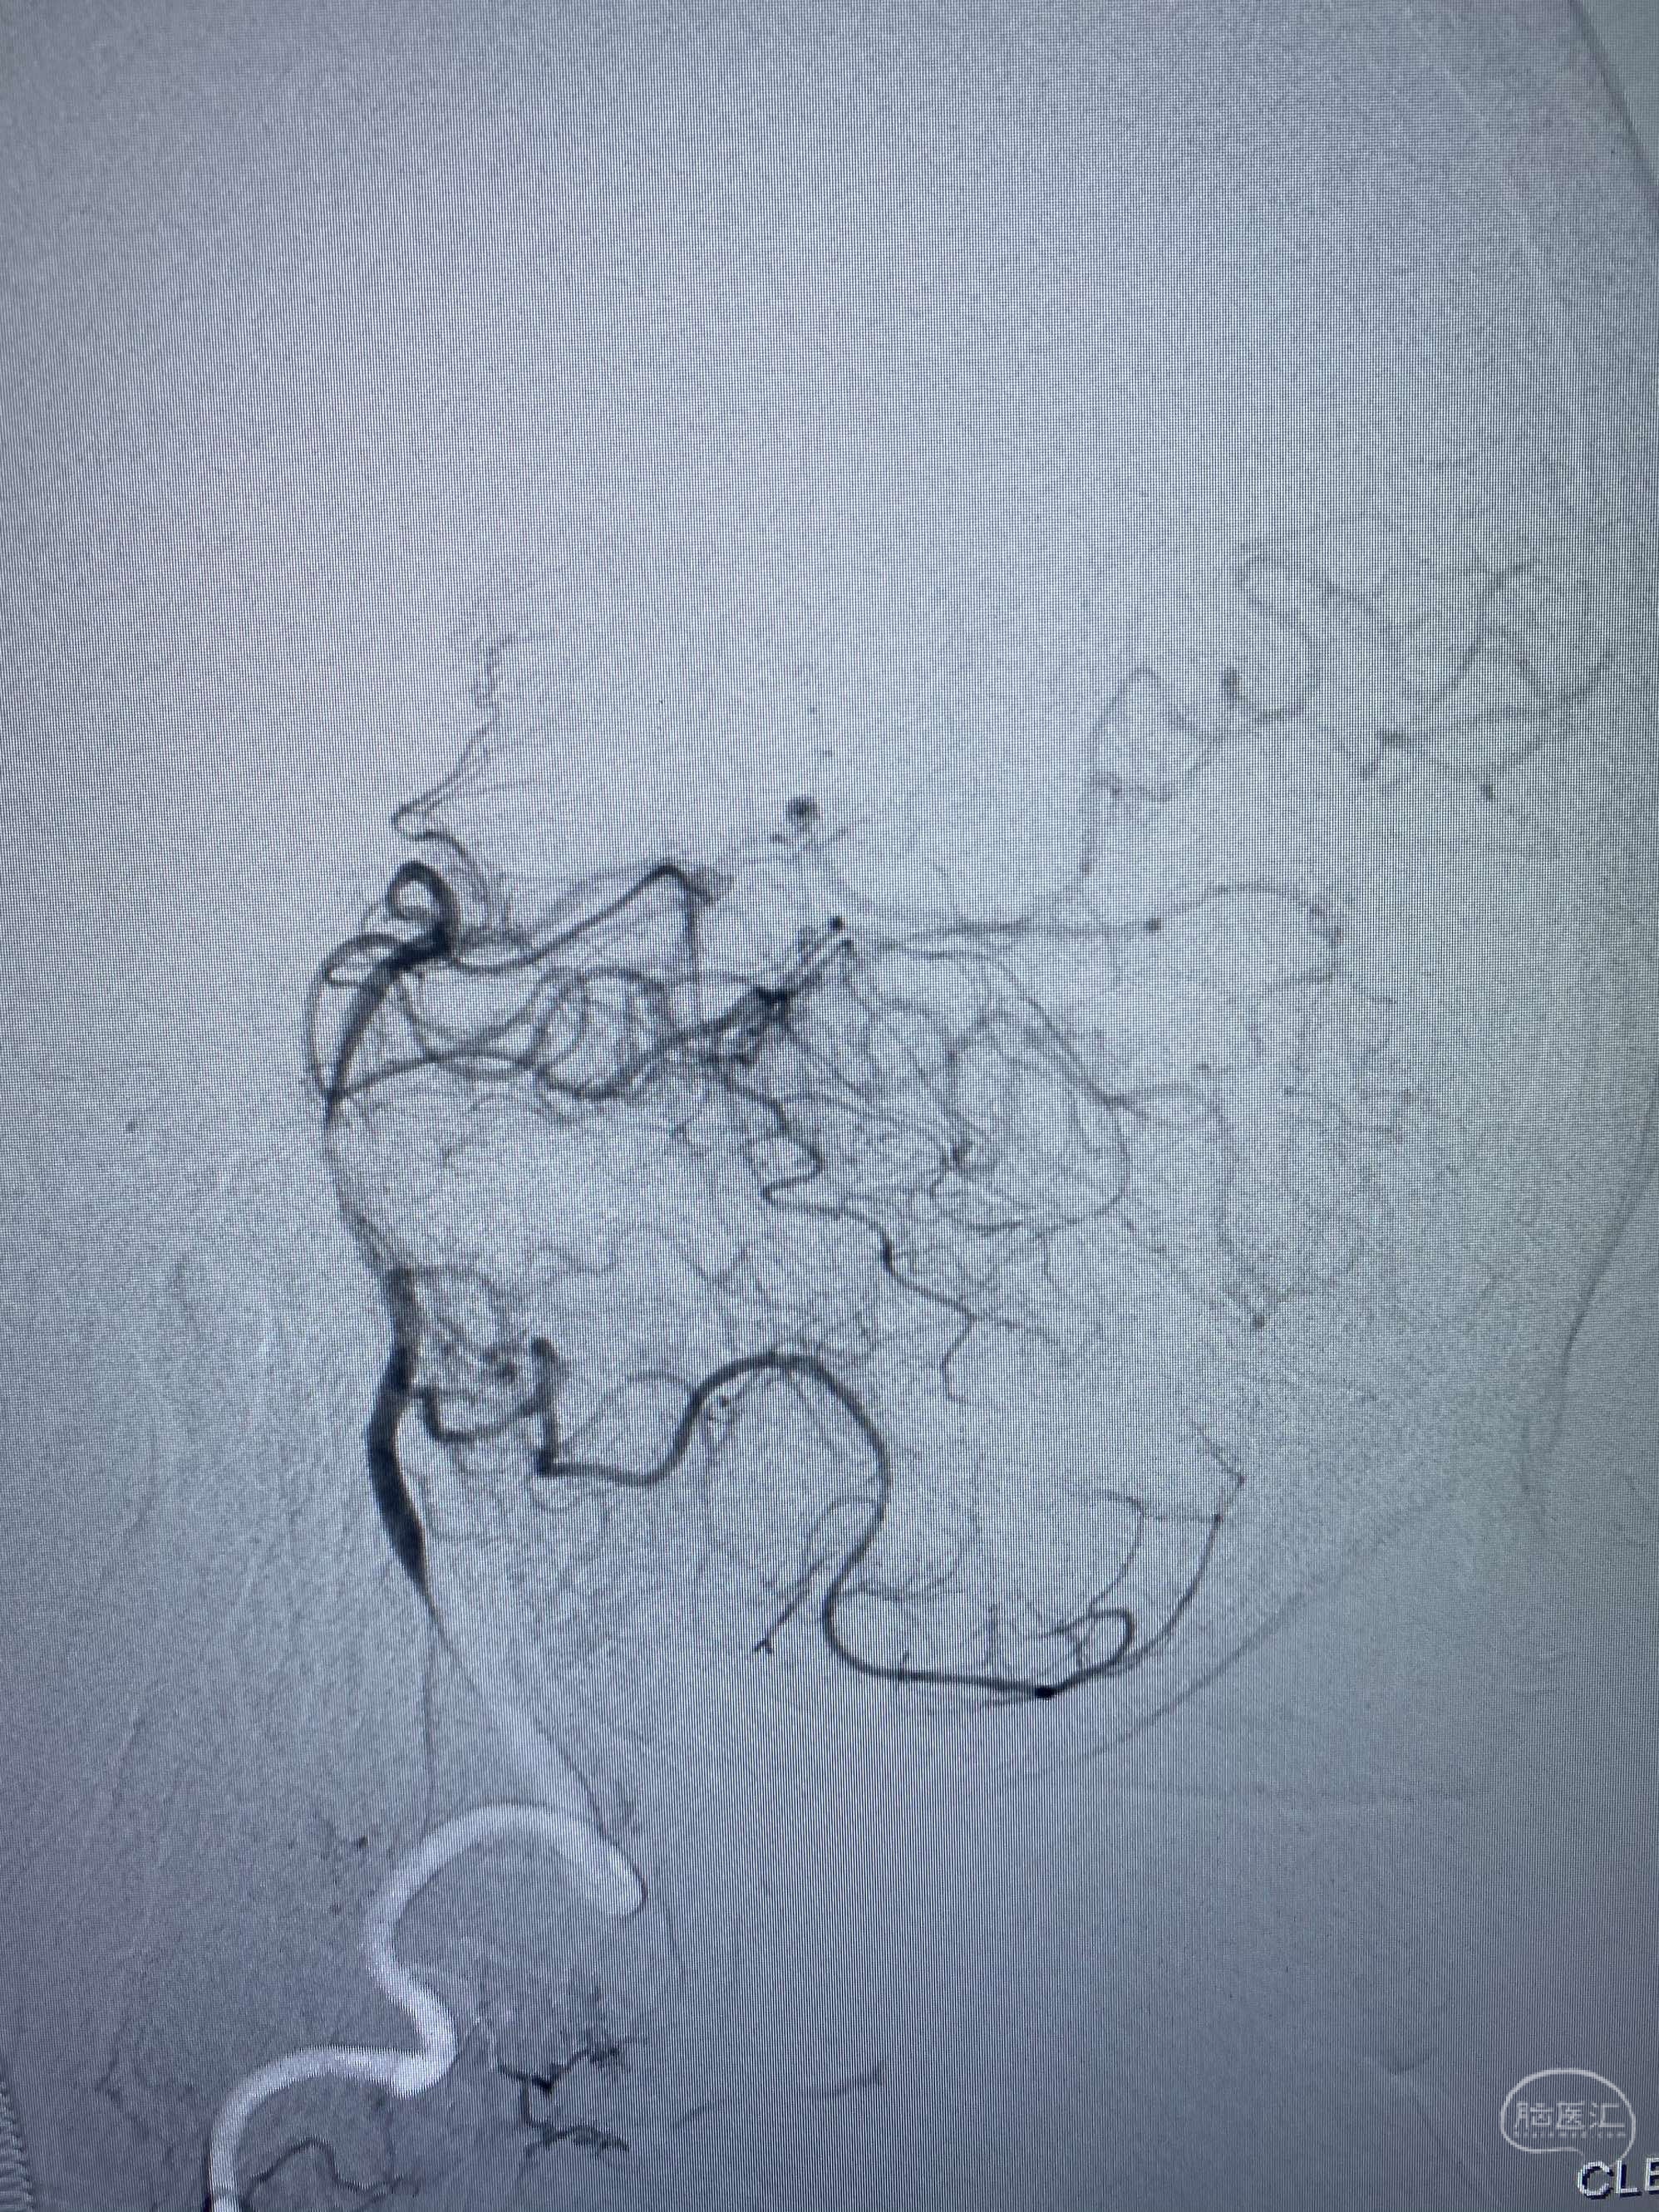

MLS,M79Y,sah,双侧MCA烟雾病,Heubner返动脉瘤,前交通段开窗,细支发出Heubner返动脉,瘤颈细长,瘤颈口比微导管细,弹簧圈2mmx3cm“隔山打牛”填塞治愈,Heubner返动脉保留。

该患者术后2天观察神志清楚,四肢活动正常。

Heubner返动脉是由大脑前动脉A1末端发出的豆纹动脉,由于走形和A1段相反,故称Heubner返动脉,该动脉梗塞可能引起尾状核头梗塞,引起偏瘫和面瘫,便身震颤等症状。